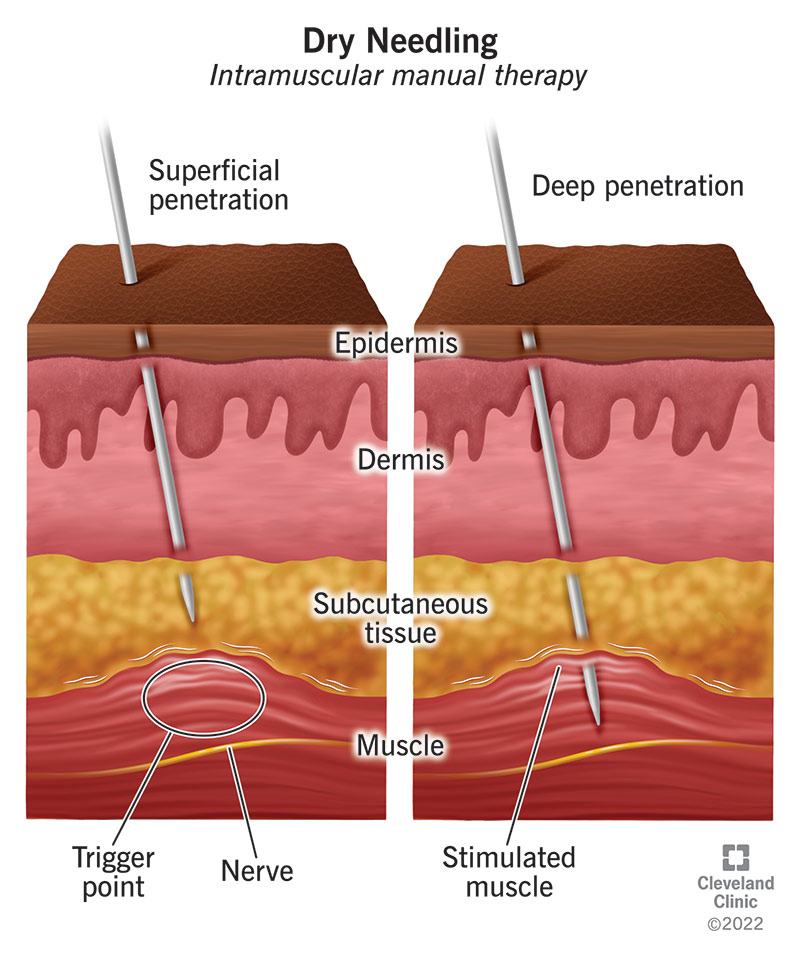

What Is Dry Needling?

Dry needling – Isn’t that like acupuncture?

What is Dry Needling? – Professional Physical Therapy Houston

What is Dry Needling? – Advanced Physical Therapy Specialists

What Is Dry Needling? – [𝗣]𝗥𝗲𝗵𝗮𝗯

What is Dry Needling and how can it help? – Total Sports Therapy

What is dry needling? – Momentum Physical Therapy | Pueblo, CO

Everything You Need To Know About Dry Needling – PRO Therapy

What is dry needling and how can it benefit me? – MediPhysio